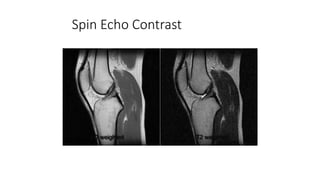

Spin Echo Contrast

T1 weighted T2 weighted

PD weighted T2 weighted